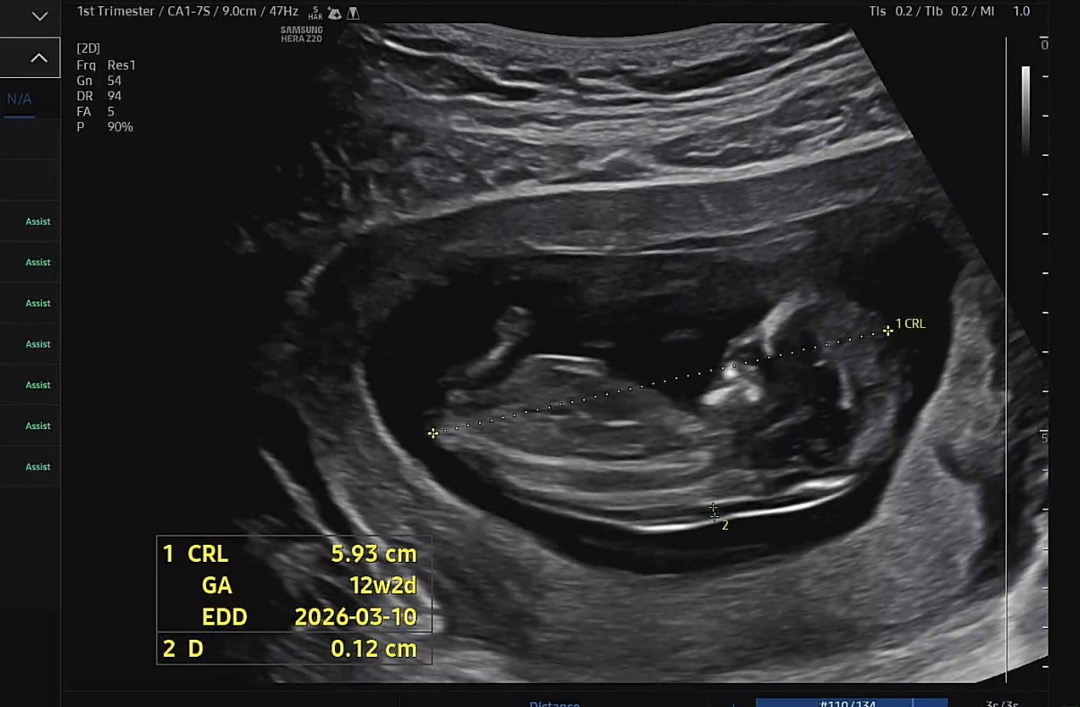

2026년 3월 베동

12주 2일이구요! 이제 4주 뒤에 병원을 가는데 너무너무 궁금해서요🙊 미리 감사드립니당💝